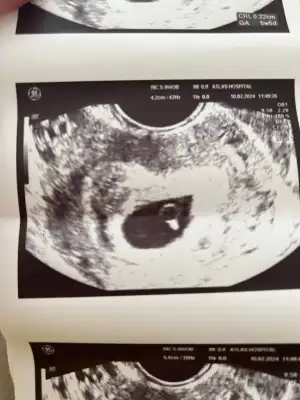

Kızlar 6+1 vajinal ultrason banada bakarmısınız

Eklentiler

• IMG_6314.webp